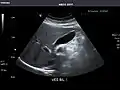

Gallbladder -

Gallbladder

Gallbladder: No stones, wall thickening, or pericholecystic fluid.

Common Bile Duct: Nondilated measuring 1.3 mm at the level of the porta hepatis.